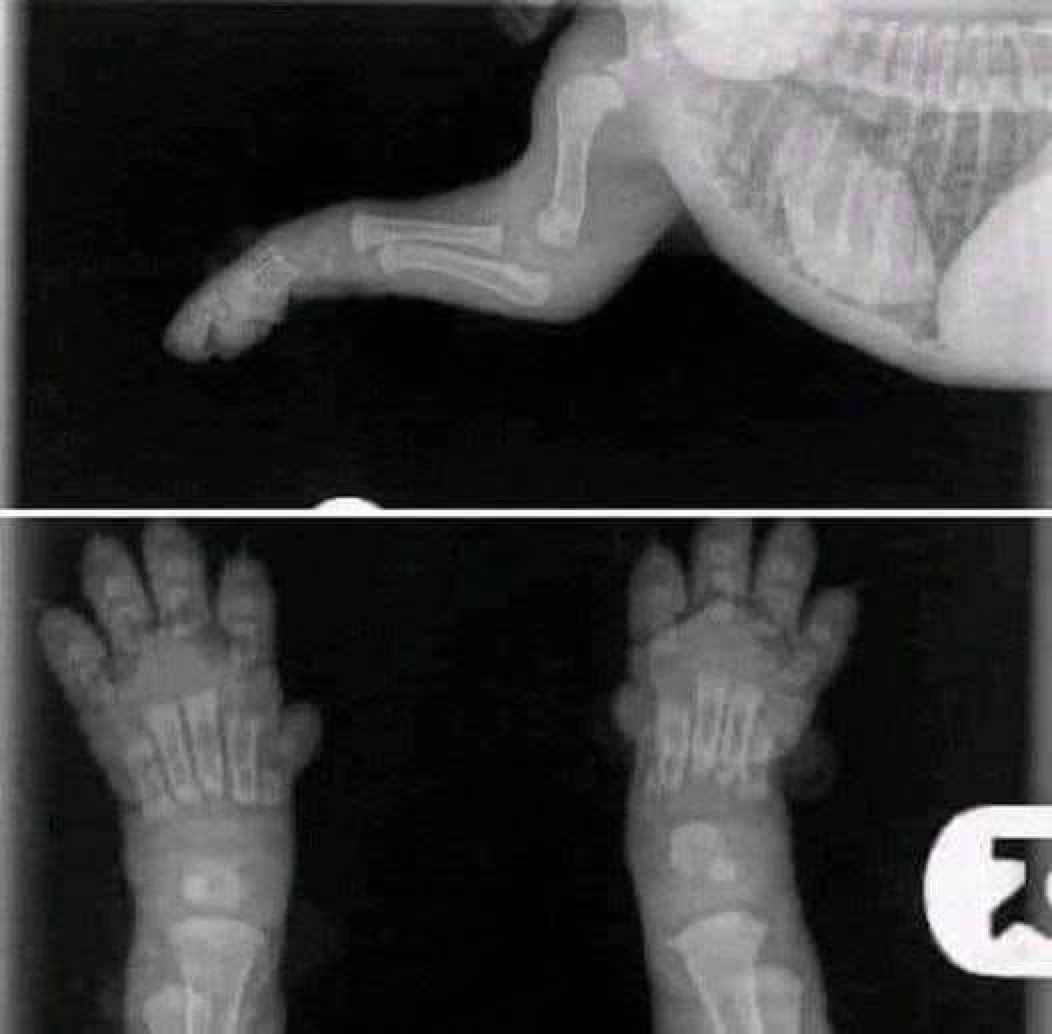

This is something everyone should see.

This xray is of a 2 week old puppy.

When you get your 8/10 week old puppies, please keep this image in mind. Their bones do not even touch yet. They plod around so cutely with big floppy paws and wobbly movement because their joints are entirely made up of muscle, tendons, ligaments with skin covering. Nothing is fitting tightly together or has a true socket yet.

When you run them excessively or don't restrict their exercise to stop them from overdoing it during this period you don't give them a chance to grow properly. Every big jump or excited bouncing run causes impacts between the bones. In reasonable amounts this is not problematic and is the normal wear and tear that every animal will engage in.

But when you're letting puppy jump up and down off the lounge or bed, take them for long walks/hikes, you are damaging that forming joint. When you let the puppy scramble on tile with no traction you are damaging the joint.

You only get the chance to grow them once. A well built body is something that comes from excellent breeding and a great upbringing-BOTH, not just one.

Once grown - around 12-18 months depending on their breed, you will have the rest of their life to spend playing and engaging in higher impact exercise. So keep it calm while they're still little baby puppies and give the gift that can only be given once.